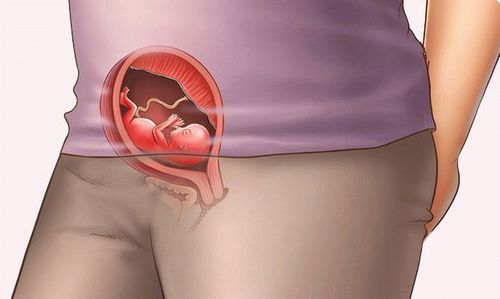

Розмір плоду на 14 тижні вагітності досягає вже 9 см, а вага - близько 40 м Більш того, на фото плода видно, що кінцівки дитини вже практично сформувалися!

На початку другого триместру середнє зростання малюка становитьприблизно 12-13 см, вага 35-52 грама. Це період активного росту дитини, до 27-го тижня плід додасть у вазі більше 1 кг і потроїть зростання.

Все більше вдосконалюються лицьові кістки плода, чітко виділяється ніс, лоб. Починають працювати м'язи обличчя, дитина рухає бровами, хмуриться, періодично змінюється його міміка. На голові починають рости волосся. Якщо дивитися на екран УЗД, то можна побачити, як дитина вже може намагатися координувати свої рухи. Ембріон вміє стискати і розтискати кулаки, смоктати пальчик, рухати ногами і руками.

Шкіра плоду прозора, крізь неї просвічують судини, внутрішні органи. Вже сформувалися на пальчиках індивідуальні малюнки, які залишаться на все життя. Дитина вже може ковтати і тому час від часу заковтує навколоплідні води.

Збільшується рухова активність плода, але відчує її мама нескоро, все тому, що в 14 тижнів малюкові ще просторо в животі. Якщо жінка готується стати матір'ю вперше, то відчуття руху або «метеликів» в животі, виникне на терміні від 18-20 тижнів. Якщо жінка вже народжувала, то вже через два-три тижні вона може відчути переміщення малюка в животі. Всі відчуття дуже індивідуальні, деякі відчувають поштовх, інші порівнюють відчуття з газами.

Довжина Вашого малюка тепер 8-9 см, вага - 43 грами. У дитинку починають рости маленькі волоссячко, які покриють усі його тіло і допомагатимуть йому зберігати тепло. Це йому зараз особливо необхідно, тому що його шкіра ще дуже тонка, і зовсім немає підшкірної жирової клітковини. Коли вона з'явиться в достатній кількості (через кілька місяців), Пушкова волоски відпадуть і будуть входити до складу мекония - вмісту кишечника, яке відходить через деякий час після пологів.